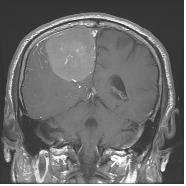

뇌교종은 뇌를 구성하고 있는 신경세포와 이를 지지하는 교세포 중 교세포에서 기원하는 종양을 의미하며, 악성뇌교종이란 뇌교종 중 그 특성이 악성을 보이는 종양을 통틀어 일컫는 포괄적인 용어입니다. 뇌 내에서 생기는 뇌교종의 경우 뇌 밖에서 생기는 종양이 대부분 양성인 것과 달리 침습적인 성장을 하며 경계가 불분명하고 악성인 경우가 많습니다. 교종 중 절반 이상이 악성이며, 양성인 신경교종도 시간이 경과하면서 악성화 되는 경향이 있습니다. 좁은 의미로는 이러한 종양 중 빈도가 가장 많고 악성도 역시 가장 높은 교모세포종을 악성뇌교종이라고 합니다. 국내에서는 연간 약 600여명의 환자가 발생하는 것으로 추정되며 특히 40세 이후에 발생빈도가 높습니다. 서양에 비해 발생빈도가 다소 낮은 편입니다.